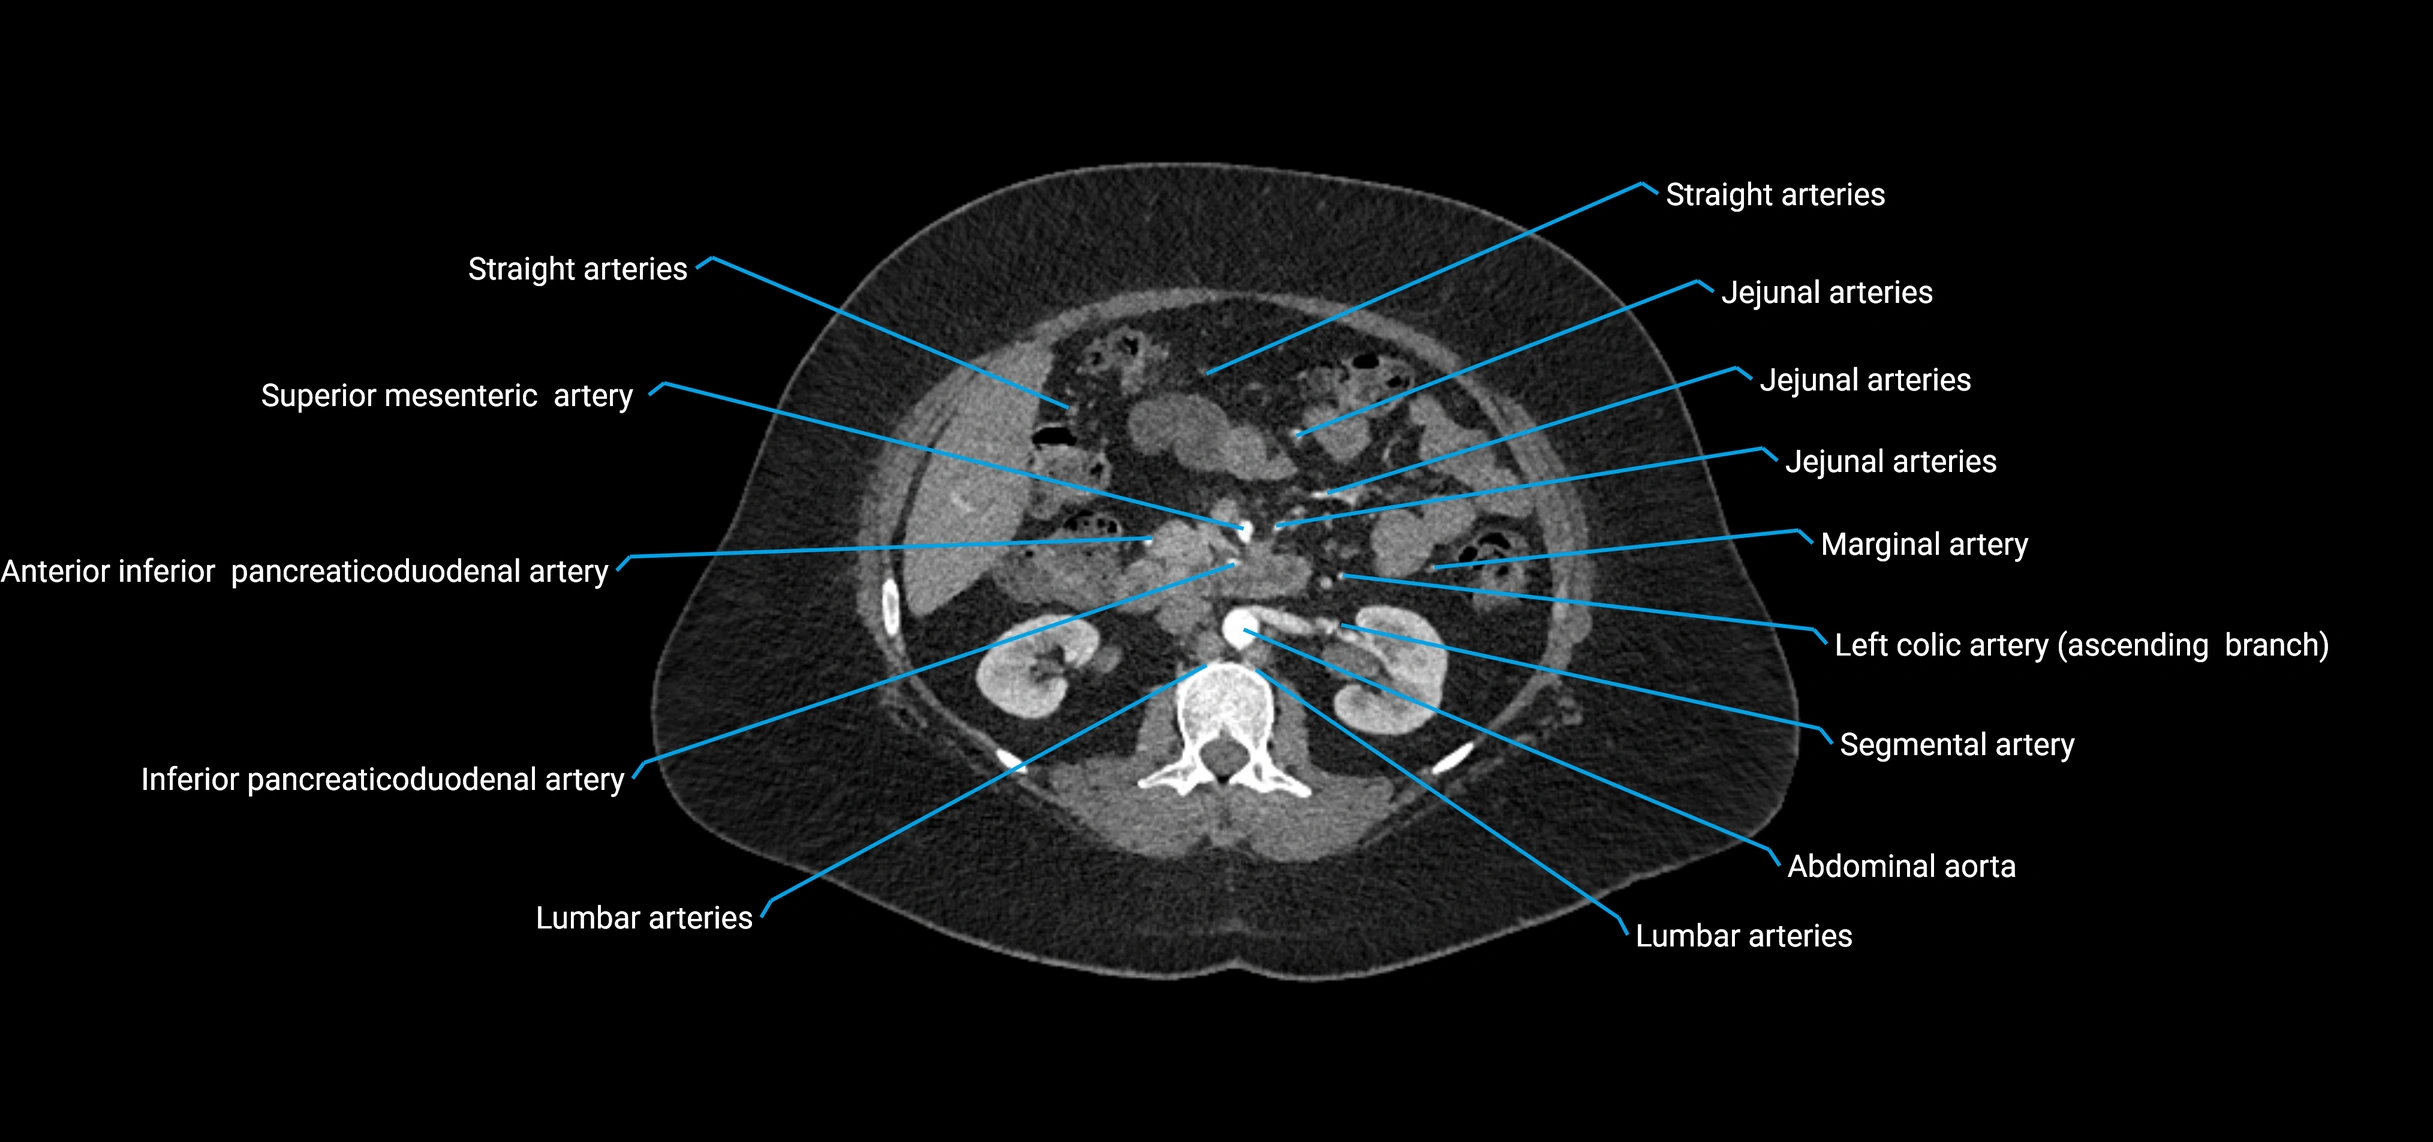

Contrast-enhanced CT (CTA):

• Gold standard for abdominal aortic imaging

• Provides excellent detail of lumen, wall, aneurysm, thrombus, and branch vessels

• Multiplanar and 3D reconstructions help in aneurysm measurement, stent graft planning, and dissection evaluation